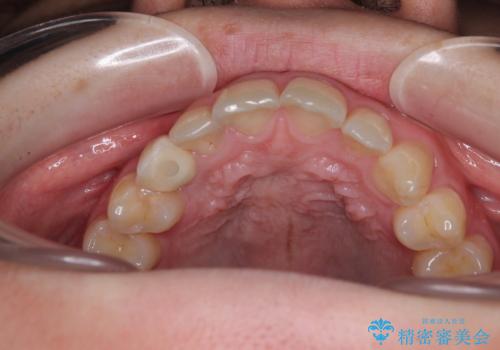

- 永久歯が生えてこず、欠損になっていることを気にして来院された患者様です。

CT撮影を行ったところ、埋もれている犬歯を牽引して萌出させることは不可能と判断し、インプラントによる補綴治療を行うこととしました。